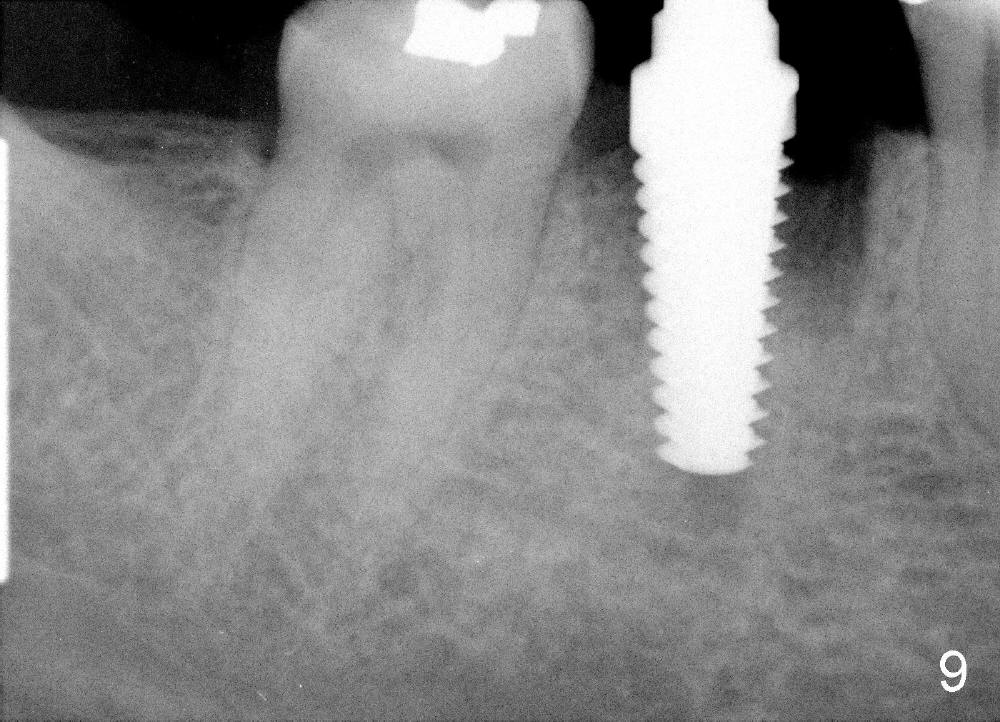

A 38-year-old lady agrees to have implant placement 7 years after loss of the crown of the lower right first molar (Fig.1,2). When the tooth is extracted, the septum is found to be low (Fig.3,4). To confirm it, a PA is taken (Fig.5). To initiate an osteotomy in the septum, it is trans-sectioned with thin osteotomes as shown in Fig.4 insert (black line). A 2 mm pilot drill is placed in the septum (Fig.6: P). The osteotomy is enlarged by 2.5-4.0 mm reamers (Fig.7,8), followed by insertion of 6x17 mm tapered tap at the depth 14 mm (Fig.9). The osteotomy is further enlarged by 4.5 and 5.0 mm reamers. A 6.0x14 mm one piece implant is placed initially. The trajectory is not ideal. A 6.0x14 mm one piece implant is placed initially. The trajectory is not ideal. The implant is removed from the osteotomy partially and reinserted with improved trajectory (Fig.11, compare to Fig.10 (red line)). Primary stability is high. There is not much bone mesiodistally so that the trajectory is easily changed in that direction. After abutment preparation, mixture of autogenous bone (harvested from reamers) and allograft is placed in the residual mesial and distal sockets (Fig.12). To contain the bone graft, an immediate provisional is placed (Fig.13 P). The occlusal plane of the provisional is significantly lower than that of the adjacent teeth to avoid micromovement of the implant. The patient is advised to eat soft food on the left side. Six days postop, the patient returns for prophy. The provisional is removed; the bone graft appears to be incorporating into the socket (Fig.14). After recementation, the provisional remains in place for 3.5 months; PA shows increased bone density in the mesial and distal sockets (Fig.15, compare to Fig.5,11). Due to insurance coverage, the patient defers fabrication of definitive restoration for at least 7 months. The immediate provisional is finally lost 8.5 months postop: the gingiva attaches to the 1-piece implant (Fig.16), while the density of the mesial socket increases (Fig.17 *) with formation of the cortex (lamina dura) coronally (v). Before the provisional (Fig.18 P) is removed for cementation of the definitive restoration, black shadow (*) is noted over the buccal gingiva. It is partially due to buccal placement (Fig.19) and partially due to buccal atrophy over a period of 10.5 months postop. How to prevent buccal placement? Positioning the first pilot drill in the septum buccolingually is a key. Eleven months post crown (Fig.20 C) cementation, the black shadow remains, but there is no tenderness. If the implant threads are immediately underneath the periosteum, there is tenderness.